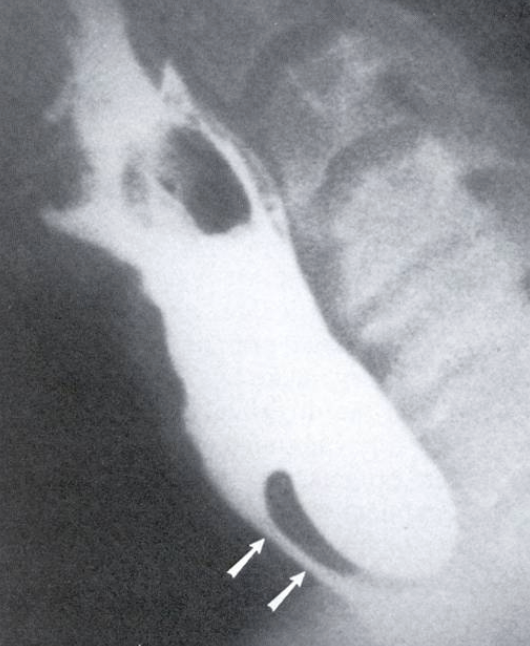

<p>What esophageal disorder is this?</p>

What esophageal disorder is this?

Schatzki’s ring